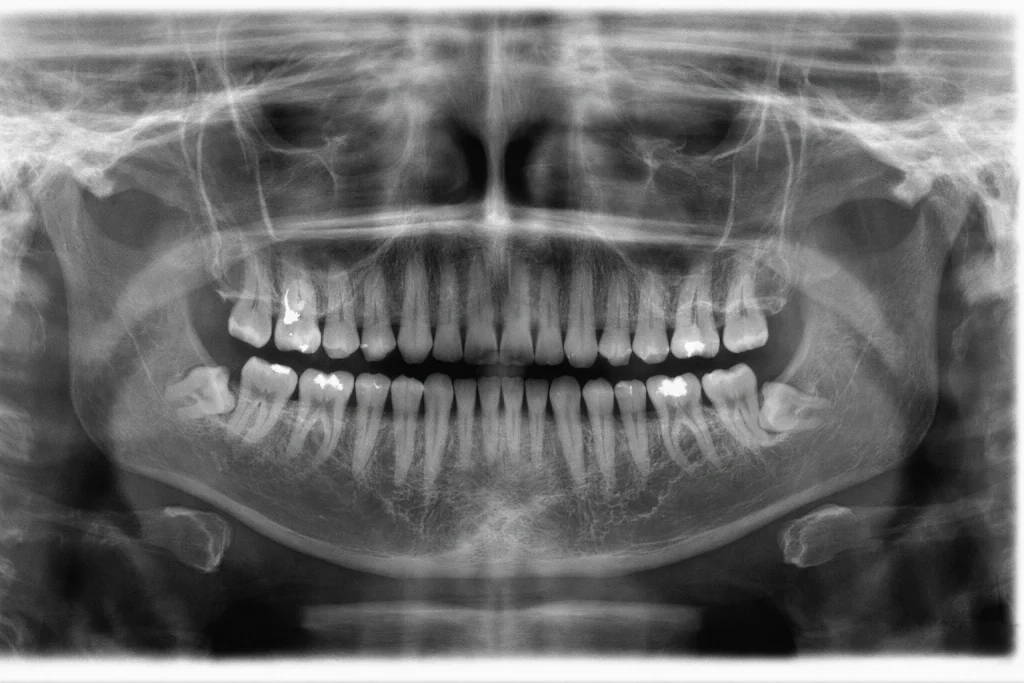

Za online pregled preporučuje se da uz fotografije pošaljete i ortopan snimak (panoramski RTG), jer omogućava precizniju procjenu stanja zuba i kosti, ali nije obavezan.

Ukoliko nemate snimak, možete ga uraditi po dolasku u MR Kliniku. Ako ga radite u inostranstvu, važno je da obuhvata kompletan prikaz zuba i korijena.

Snimak pošaljite kao fajl putem WhatsApp ili Viber aplikacije, a ne kao fotografiju odštampanog snimka, kako bi se sačuvala maksimalna jasnoća.